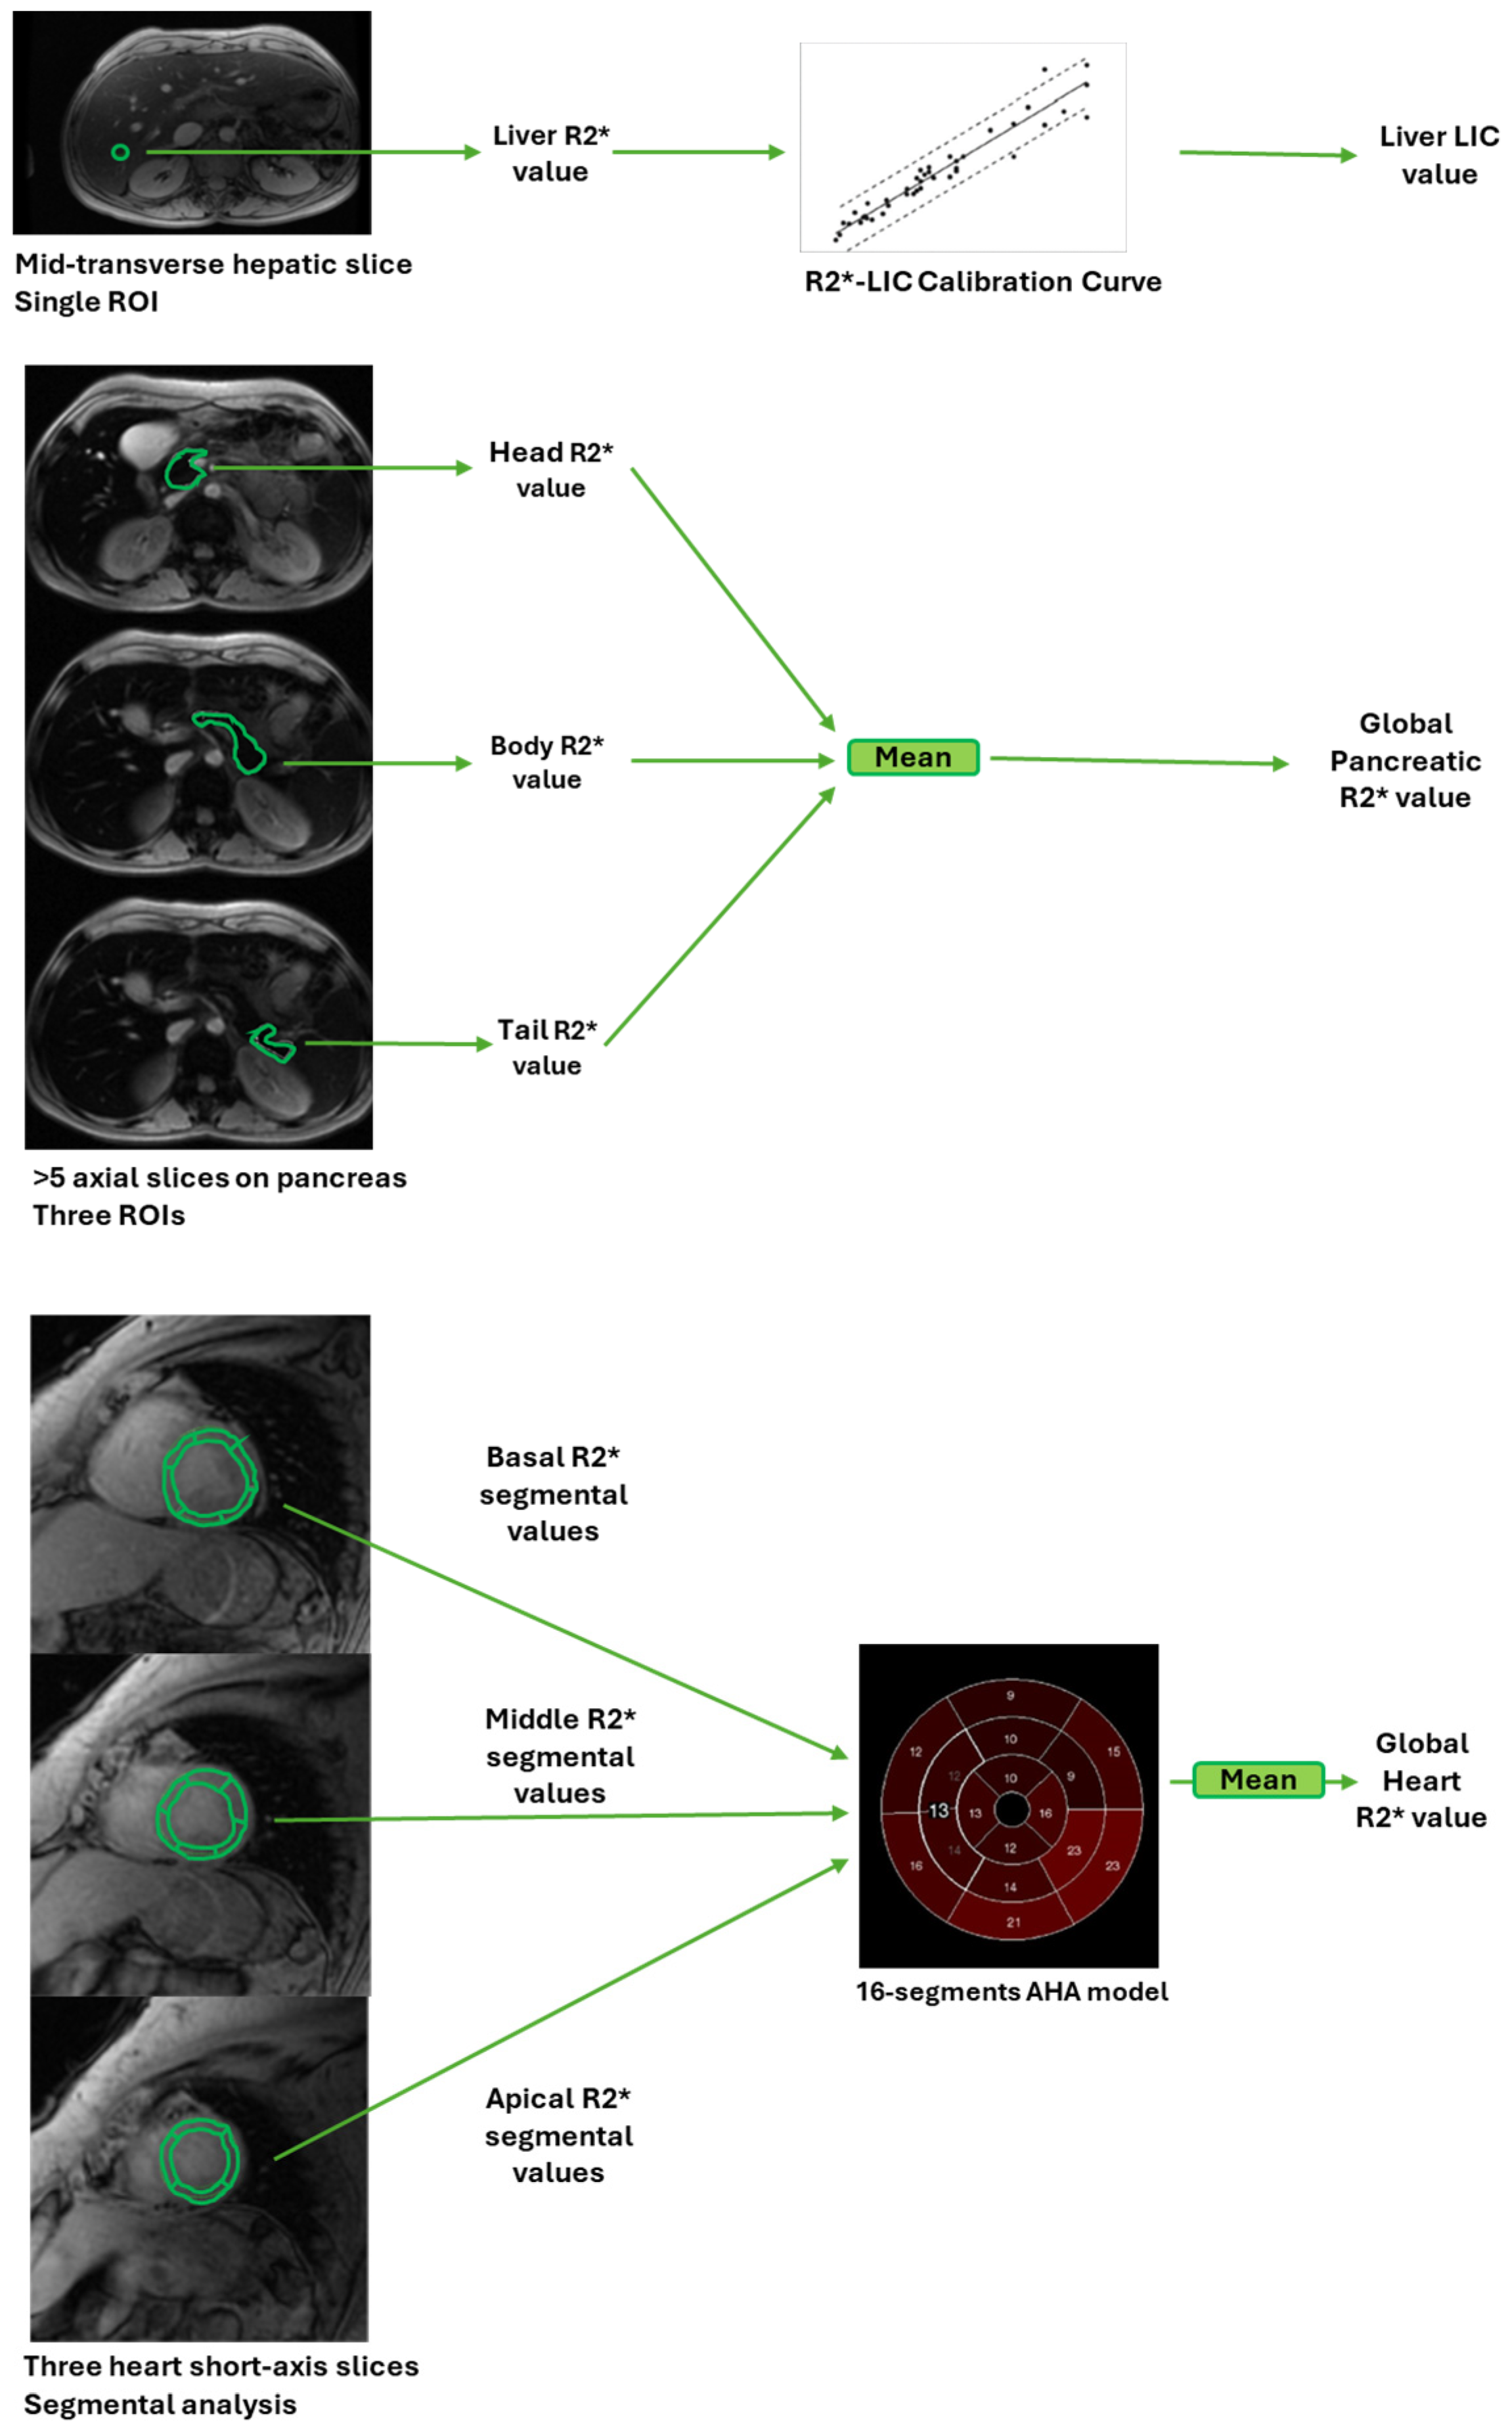

2.2. Magnetic Resonance Imaging

- Meloni, A.; De Marchi, D.; Pistoia, L.; Grassedonio, E.; Peritore, G.; Preziosi, P.; Restaino, G.; Righi, R.; Riva, A.; Renne, S.; et al. Multicenter validation of the magnetic resonance T2* technique for quantification of pancreatic iron. Eur. Radiol. 2019, 29, 2246–2252. [Google Scholar] [CrossRef] [PubMed]

- Restaino, G.; Meloni, A.; Positano, V.; Missere, M.; Rossi, G.; Calandriello, L.; Keilberg, P.; Mattioni, O.; Maggio, A.; Lombardi, M.; et al. Regional and global pancreatic T*(2) MRI for iron overload assessment in a large cohort of healthy subjects: Normal values and correlation with age and gender. Magn. Reson. Med. 2011, 65, 764–769. [Google Scholar] [CrossRef]

- Meloni, A.; Luciani, A.; Positano, V.; De Marchi, D.; Valeri, G.; Restaino, G.; Cracolici, E.; Caruso, V.; Dell’amico, M.C.; Favilli, B.; et al. Single region of interest versus multislice T2* MRI approach for the quantification of hepatic iron overload. J. Magn. Reson. Imaging 2011, 33, 348–355. [Google Scholar] [CrossRef] [PubMed]

- Wood, J.C.; Enriquez, C.; Ghugre, N.; Tyzka, J.M.; Carson, S.; Nelson, M.D.; Coates, T.D. MRI R2 and R2* mapping accurately estimates hepatic iron concentration in transfusion-dependent thalassemia and sickle cell disease patients. Blood 2005, 106, 1460–1465. [Google Scholar] [CrossRef] [PubMed]

- St Pierre, T.G.; Clark, P.R.; Chua-anusorn, W.; Fleming, A.J.; Jeffrey, G.P.; Olynyk, J.K.; Pootrakul, P.; Robins, E.; Lindeman, R. Noninvasive measurement and imaging of liver iron concentrations using proton magnetic resonance. Blood 2005, 105, 855–861. [Google Scholar] [CrossRef] [PubMed]

- Ramazzotti, A.; Pepe, A.; Positano, V.; Rossi, G.; De Marchi, D.; Brizi, M.G.; Luciani, A.; Midiri, M.; Sallustio, G.; Valeri, G.; et al. Multicenter validation of the magnetic resonance t2* technique for segmental and global quantification of myocardial iron. J. Magn. Reson. Imaging 2009, 30, 62–68. [Google Scholar] [CrossRef] [PubMed]

- Cerqueira, M.D.; Weissman, N.J.; Dilsizian, V.; Jacobs, A.K.; Kaul, S.; Laskey, W.K.; Pennell, D.J.; Rumberger, J.A.; Ryan, T.; Verani, M.S. Standardized myocardial segmentation and nomenclature for tomographic imaging of the heart: A statement for healthcare professionals from the Cardiac Imaging Committee of the Council on Clinical Cardiology of the American Heart Association. Circulation 2002, 105, 539–542. [Google Scholar] [PubMed]